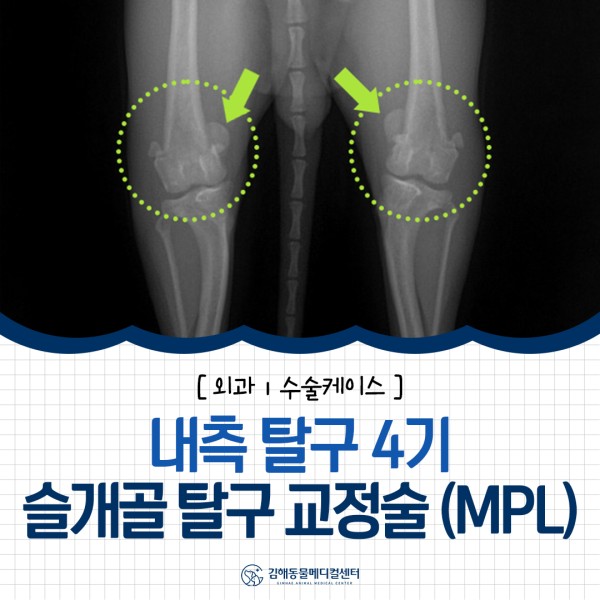

김해 강아지 슬개골 탈구 수술 전문 김해동물메디컬센터ㅣ내측 탈구 4기 MPL 교정술

정확한 상태 확인을 위한 검사를 진행한 결과,

양쪽 모두 안쪽으로 슬개골이 빠지는 내측탈구 4기 상태가 확인되었고

통증의 근본 원인을 해결하기 위해 양측 모두 슬개골 탈구 교정술(MPL)을 진행하기로 결정하였습니다.